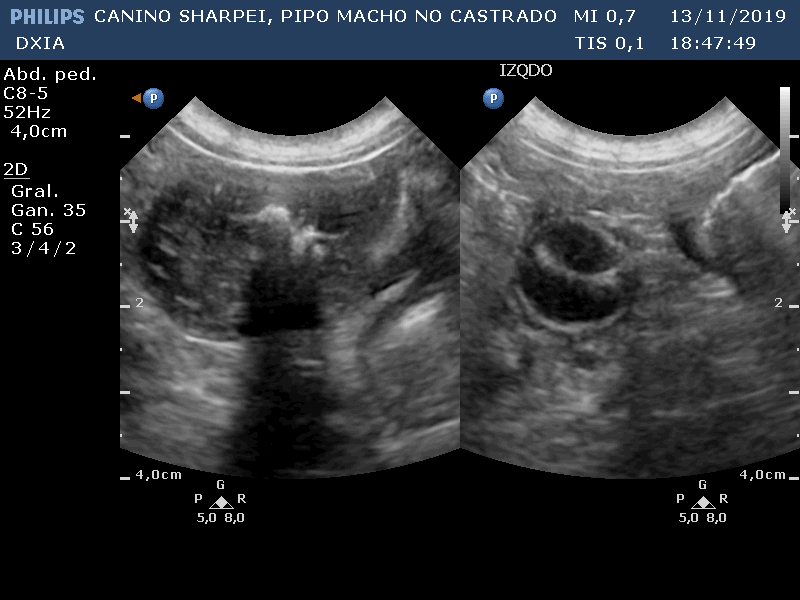

PIPO

Del informe ecográfico de Pipo se destaca la existencia de varias alteraciones:

Comentario imágenes A y B: Comparativa Asas ID normal con asa alterada donde se observa aumento de la pared (engrosamiento) con pérdida de estructura en capas.

Neoformación en ID de la que se realiza PAF ecoguiada.